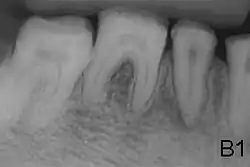

La amelogenesis imperfecta es una enfermedad genética que se presenta con formación anormal del esmalte o capa externa de los dientes. El esmalte está compuesto principalmente por mineral, que es formado y regulado por las proteínas en él. La amelogenesis imperfecta es debida al mal funcionamiento de las proteínas en el esmalte: ameloblastina, enamelina, tuftelina y amelogenina.

Las personas afectadas con amelogenesis imperfecta tienen dientes con color anormal: amarillo, marrón o gris. Los dientes tienen un mayor riesgo de sufrir cavidades dentales y son hipersensitivos a los cambios de temperatura. Este desorden puede afectar cualquier número de dientes.